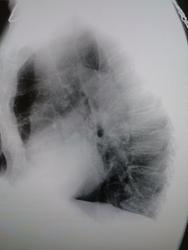

На боковом не видно, проецируется на тень сердца, может быть киста перикарда

Где та тень, и где тимус... Вот к перикарду запросто может иметь отношение. И на боковом её видно.

Да, скопия здесь не помешает. В дифряд ещё можно поставить ателектаз язычковых сегментов.Кажется, что средостение немного "уехало" влево.